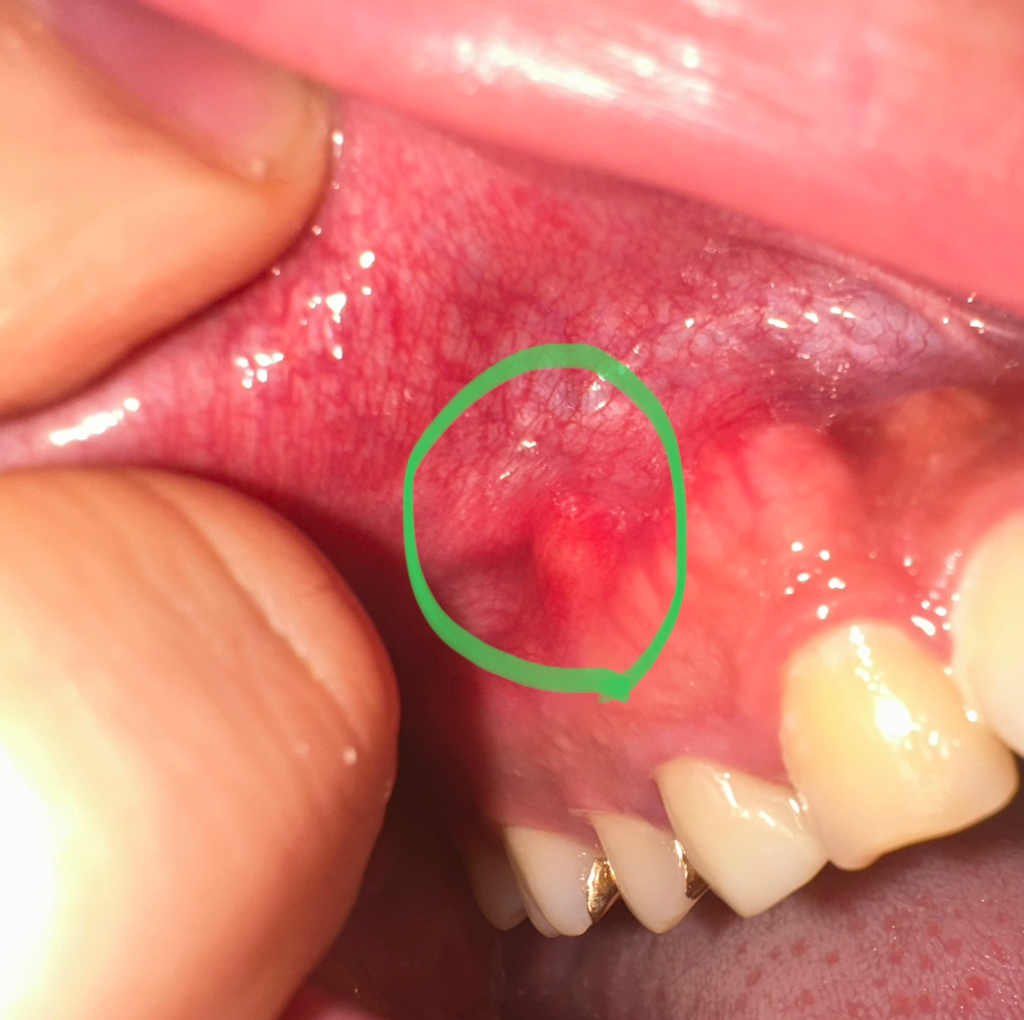

사진상으로는 농양(고름)이 맞는 것 같습니다만 정확한 진단은 치과를 가보셔야 합니다.

통증이 없으시기에 오래전부터 있었던 잇몸에서 비롯된 만성 치주농양 내지는 치아 신경(치수)에서 비롯된 만성 치조농양이 아닐까 생각됩니다.

현재 사진상으로 잇몸에 염증이 있는 것으로 보이며, 잇몸치료가 필요로 되기에 빠른시일내에 치과 방문을 권합니다.